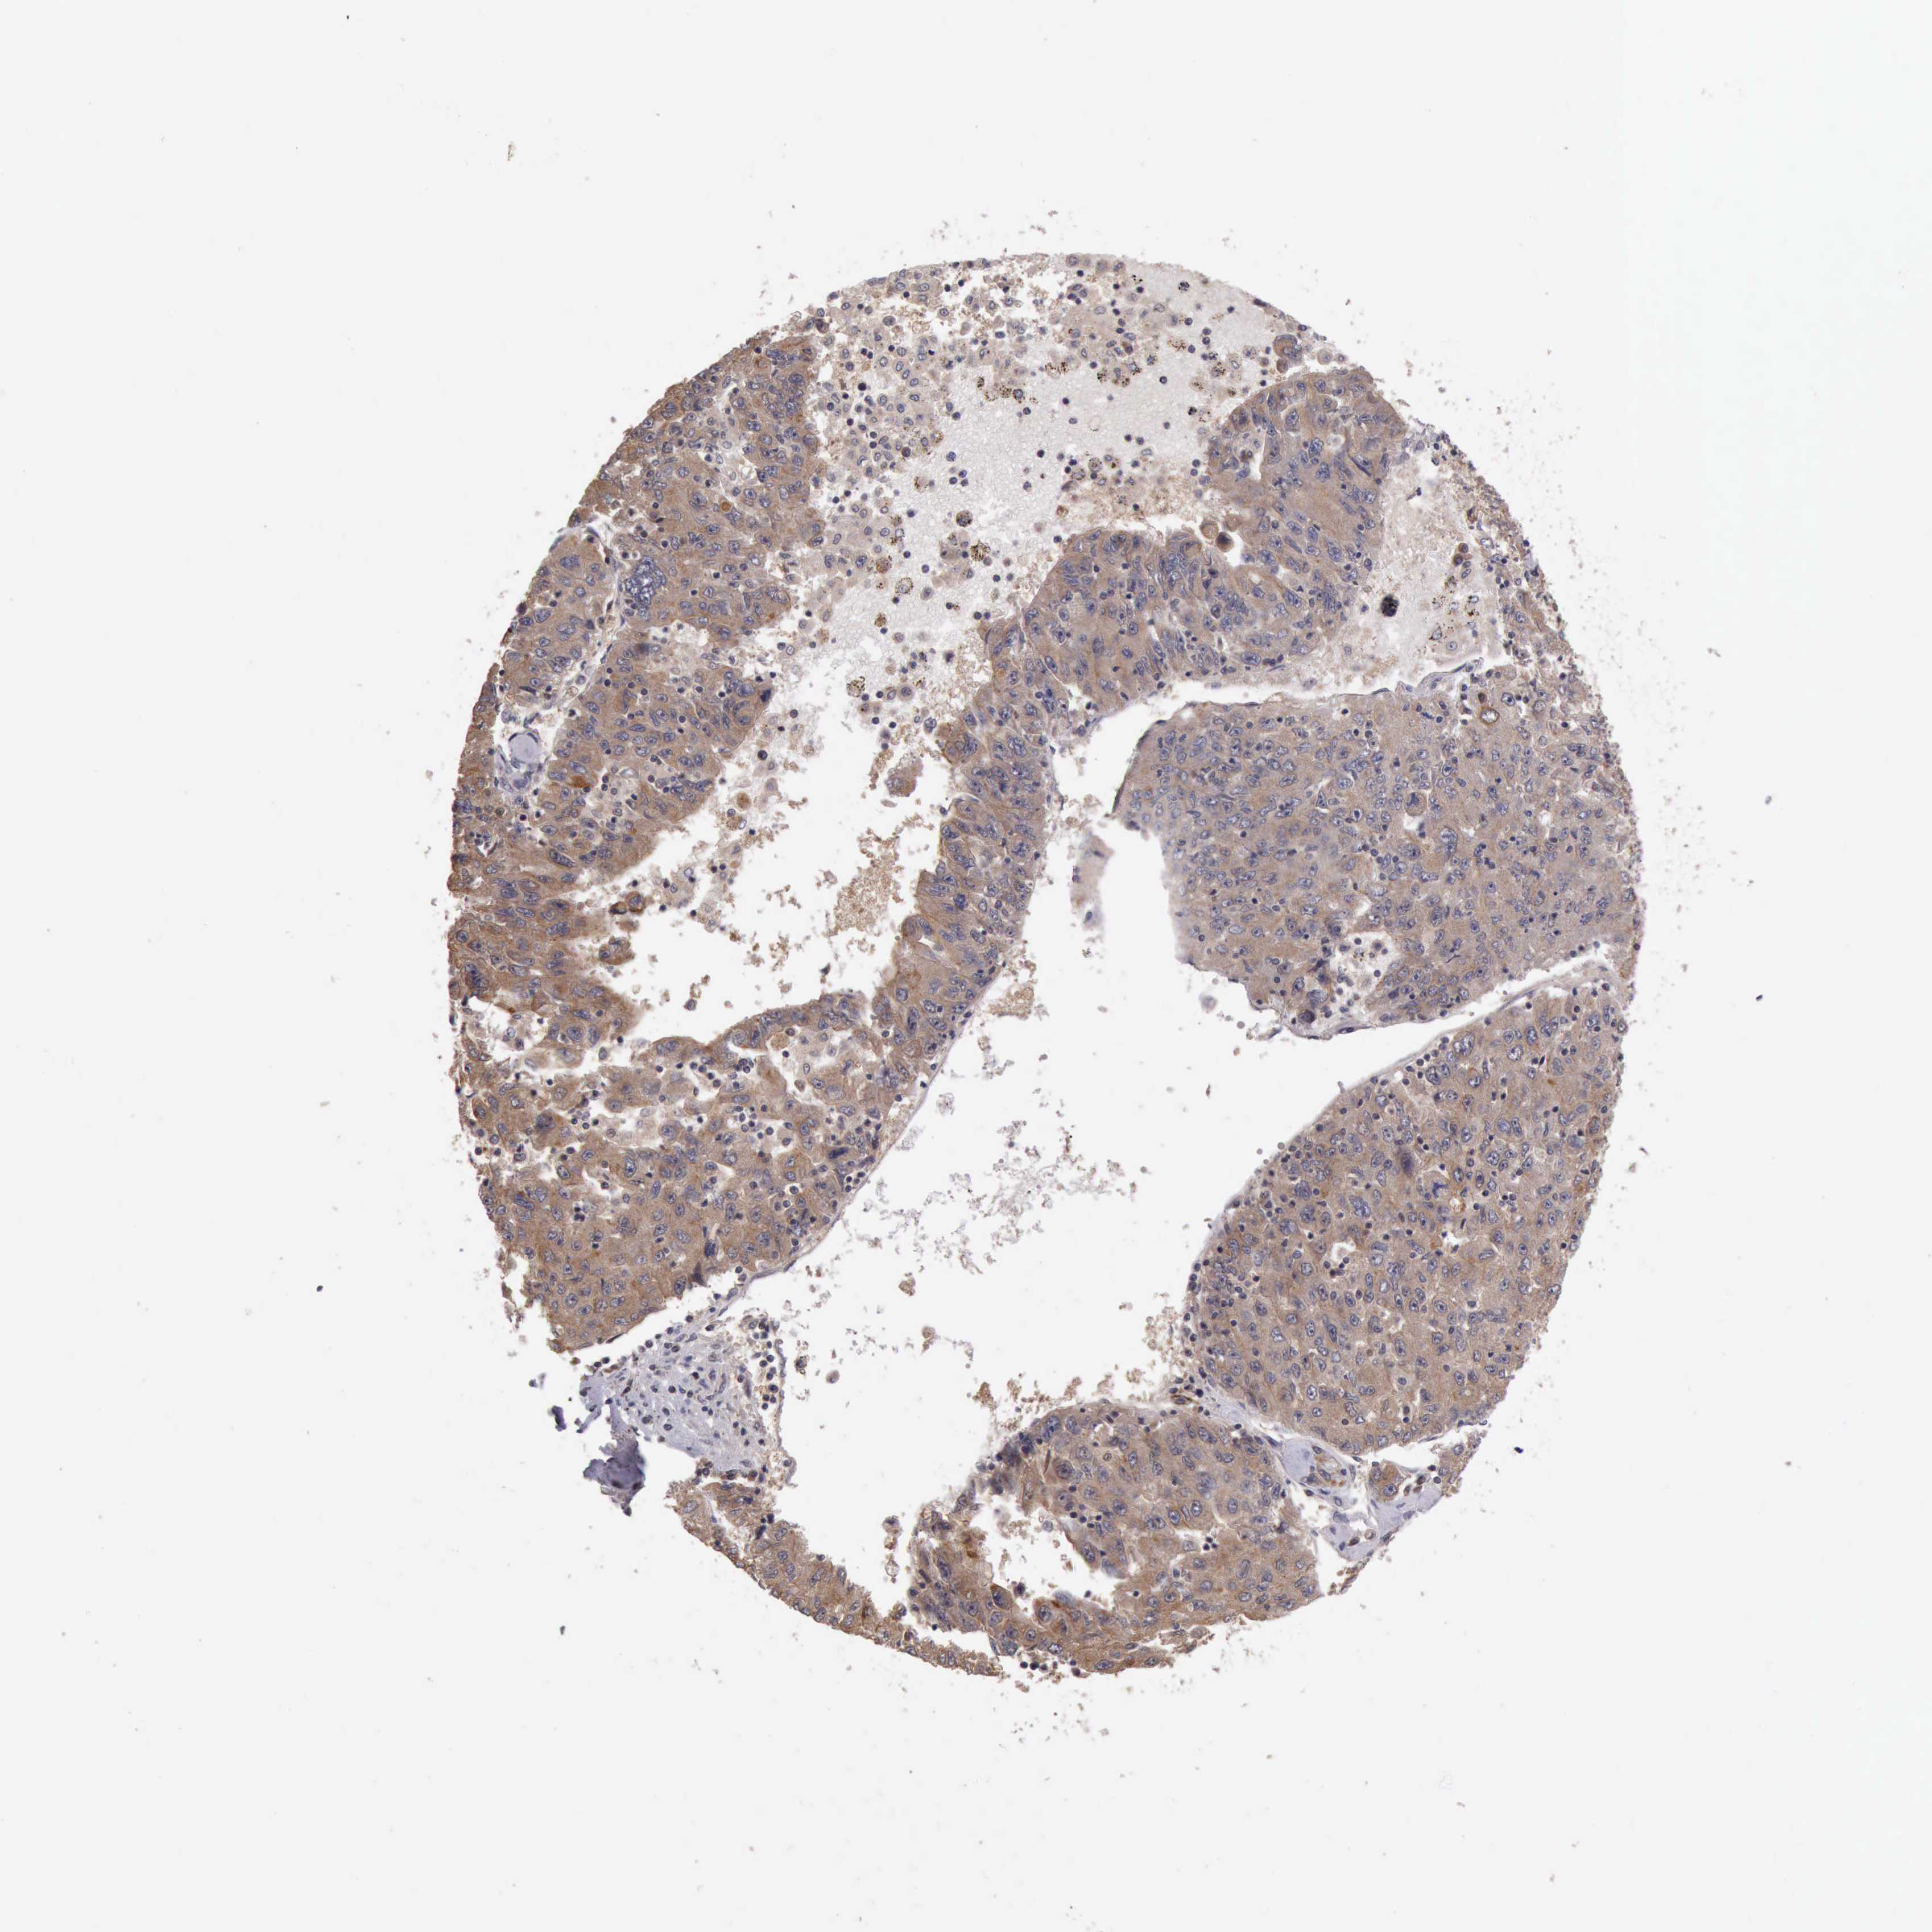

LIVER CANCER - Protein expressioni

A mouse-over function shows sample information and annotation data. Click on an image to view it in a full screen mode. Samples can be filtered based on level of antibody staining by selecting one or several of the following categories: high, medium, low and not detected. The assay and annotation is described here.

Antibody stainingi

Antibody staining in the annotated cell types in the current human tissue is reported as not detected, low, medium, or high, based on conventional immunohistochemistry profiling in selected tissues. This score is based on the combination of the staining intensity and fraction of stained cells.

Each image is clickable and will lead to virtual microscopy that enables deeper exploration of all samples and also displays staining intensity scores, fraction scores and subcellular localization as well as patient and tissue information for each sample.

Antibody HPA001114

Antibody HPA042505

Staining

High

Medium

Low

Not detected

Intensity

Strong

Moderate

Weak

Negative

Quantity

>75%

75%-25%

<25%

None

Location

Nuclear

Cytoplasmic/membranous

Cytoplasmic/membranous,nuclear

Carcinoma, Hepatocellular, NOS

Cholangiocarcinoma